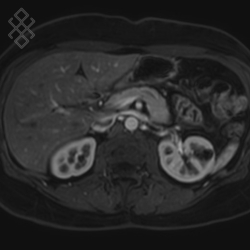

IRM des Reins / Artères rénales